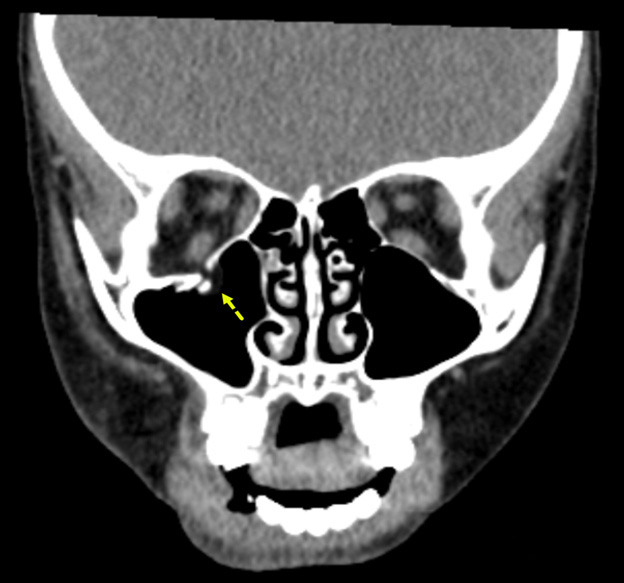

Figure 5 shows an example of an orbital floor fracture without evidence of entrapment in a pediatric patient in the coronal plane. In comparison, Figure 6 shows an entrapped orbital floor fracture in the bone window. The image reveals evidence of a non-displaced orbital fracture with entrapped intra-orbital fat.

Figure 5. Orbital Floor Fracture Without Evidence of Entrapment |

![]() |

The image shows a displaced orbital floor fracture with no evidence of entrapment. Image courtesy of Mantosh S. Rattan, MD, Radiologist, Orlando Health Arnold Palmer Children’s Hospital, Orlando, FL. |

Figure 6. Entrapped Orbital Floor Fracture |

The image shows evidence of a non-displaced orbital fracture with entrapped intra-orbital fat (bone window). Image courtesy of Mantosh S. Rattan, MD, Radiologist, Orlando Health Arnold Palmer Children’s Hospital, Orlando, FL. |